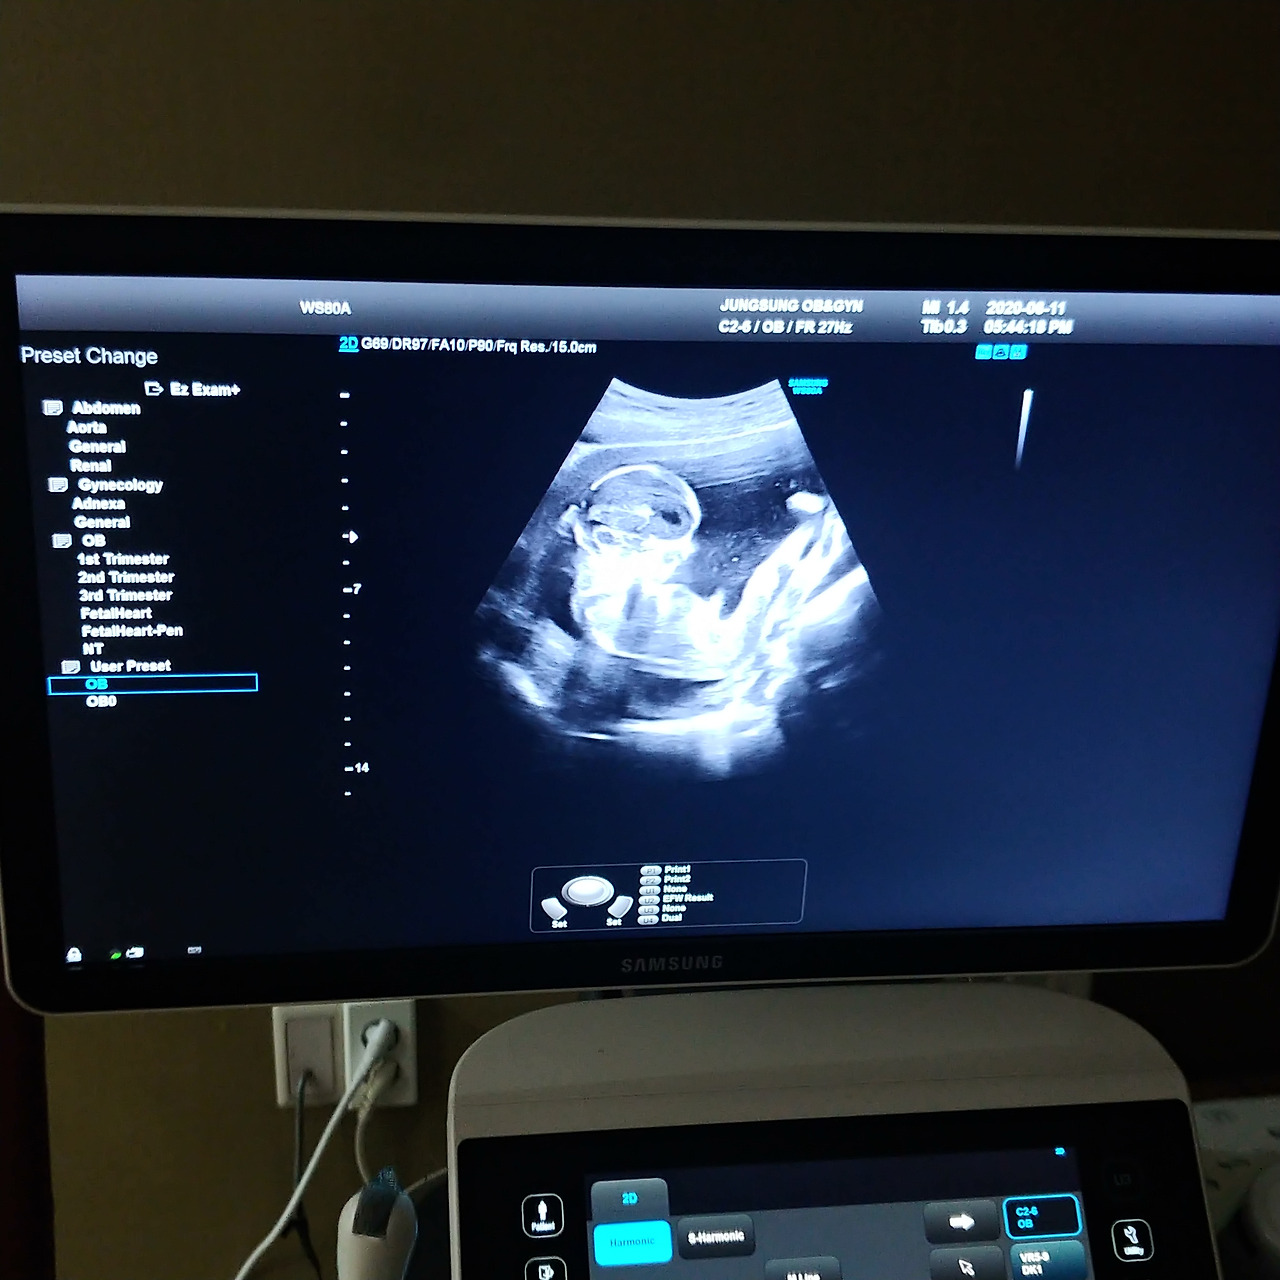

6월 11일, 임신 16주 산부인과 정기 검진하는 날이었다. 셋째의 성별을 알 수 있지 않을까 해서 전날부터 밤잠을 설쳤다. 셋째를 임신하고 온통 나의 관심사는 셋째의 성별이었으니 오죽하겠는가. 그날은 셋째가 예쁜 고명딸 일지 아니면 아내를 도울 삼총사 일지 확인할 수도 있는 일생일대의 순간이었다.

나는 지난 검진 초음파 영상을 보고 딸이라는 것을 확신했다. 그냥 예비 딸바보 아빠의 직감이랄까. 느낌이 그랬다. 초음파 영상으로 보이는 아이 모습이 이뻤다. 무의식이 무서운 게 초음파 영상을 보자마자 다리 쪽을 먼저 봤다. 나는 보자마자 속으로 쾌재를 불렀다. 초음파 영상에 성기 같아 보이는 부분이 굴곡 없이 매끄러웠다. 초음파 영상 속의 아이 움직임은 영락없이 그냥 딸의 모습이었다.

20200611_175201.jpg

나는 진료실에서 딸이라고 호들갑을 떨었다. 차분하고 조용했던 진료실의 정적을 깨고 말았다. 딸이냐며 의사 선생님을 재촉했지만 의사 선생님은 아직 모른다며 말을 아꼈다. 그 순간만큼은 내가 명의였다.

역시 예비 딸바보 아빠의 촉이 들어맞는 순간이었다. 초음파 영상을 유심히 보더니 의사 선생님이 "딸이네요!" 성별을 알려줬다. 의사 선생님이 말하는 순간 나도 모르게 웃고 말았다. 분명 마스크를 쓰고 있었는데 입가의 미소를 감출 수 없었나 보다. 아내는 나를 보고 왜 웃냐며 어이없어했다.